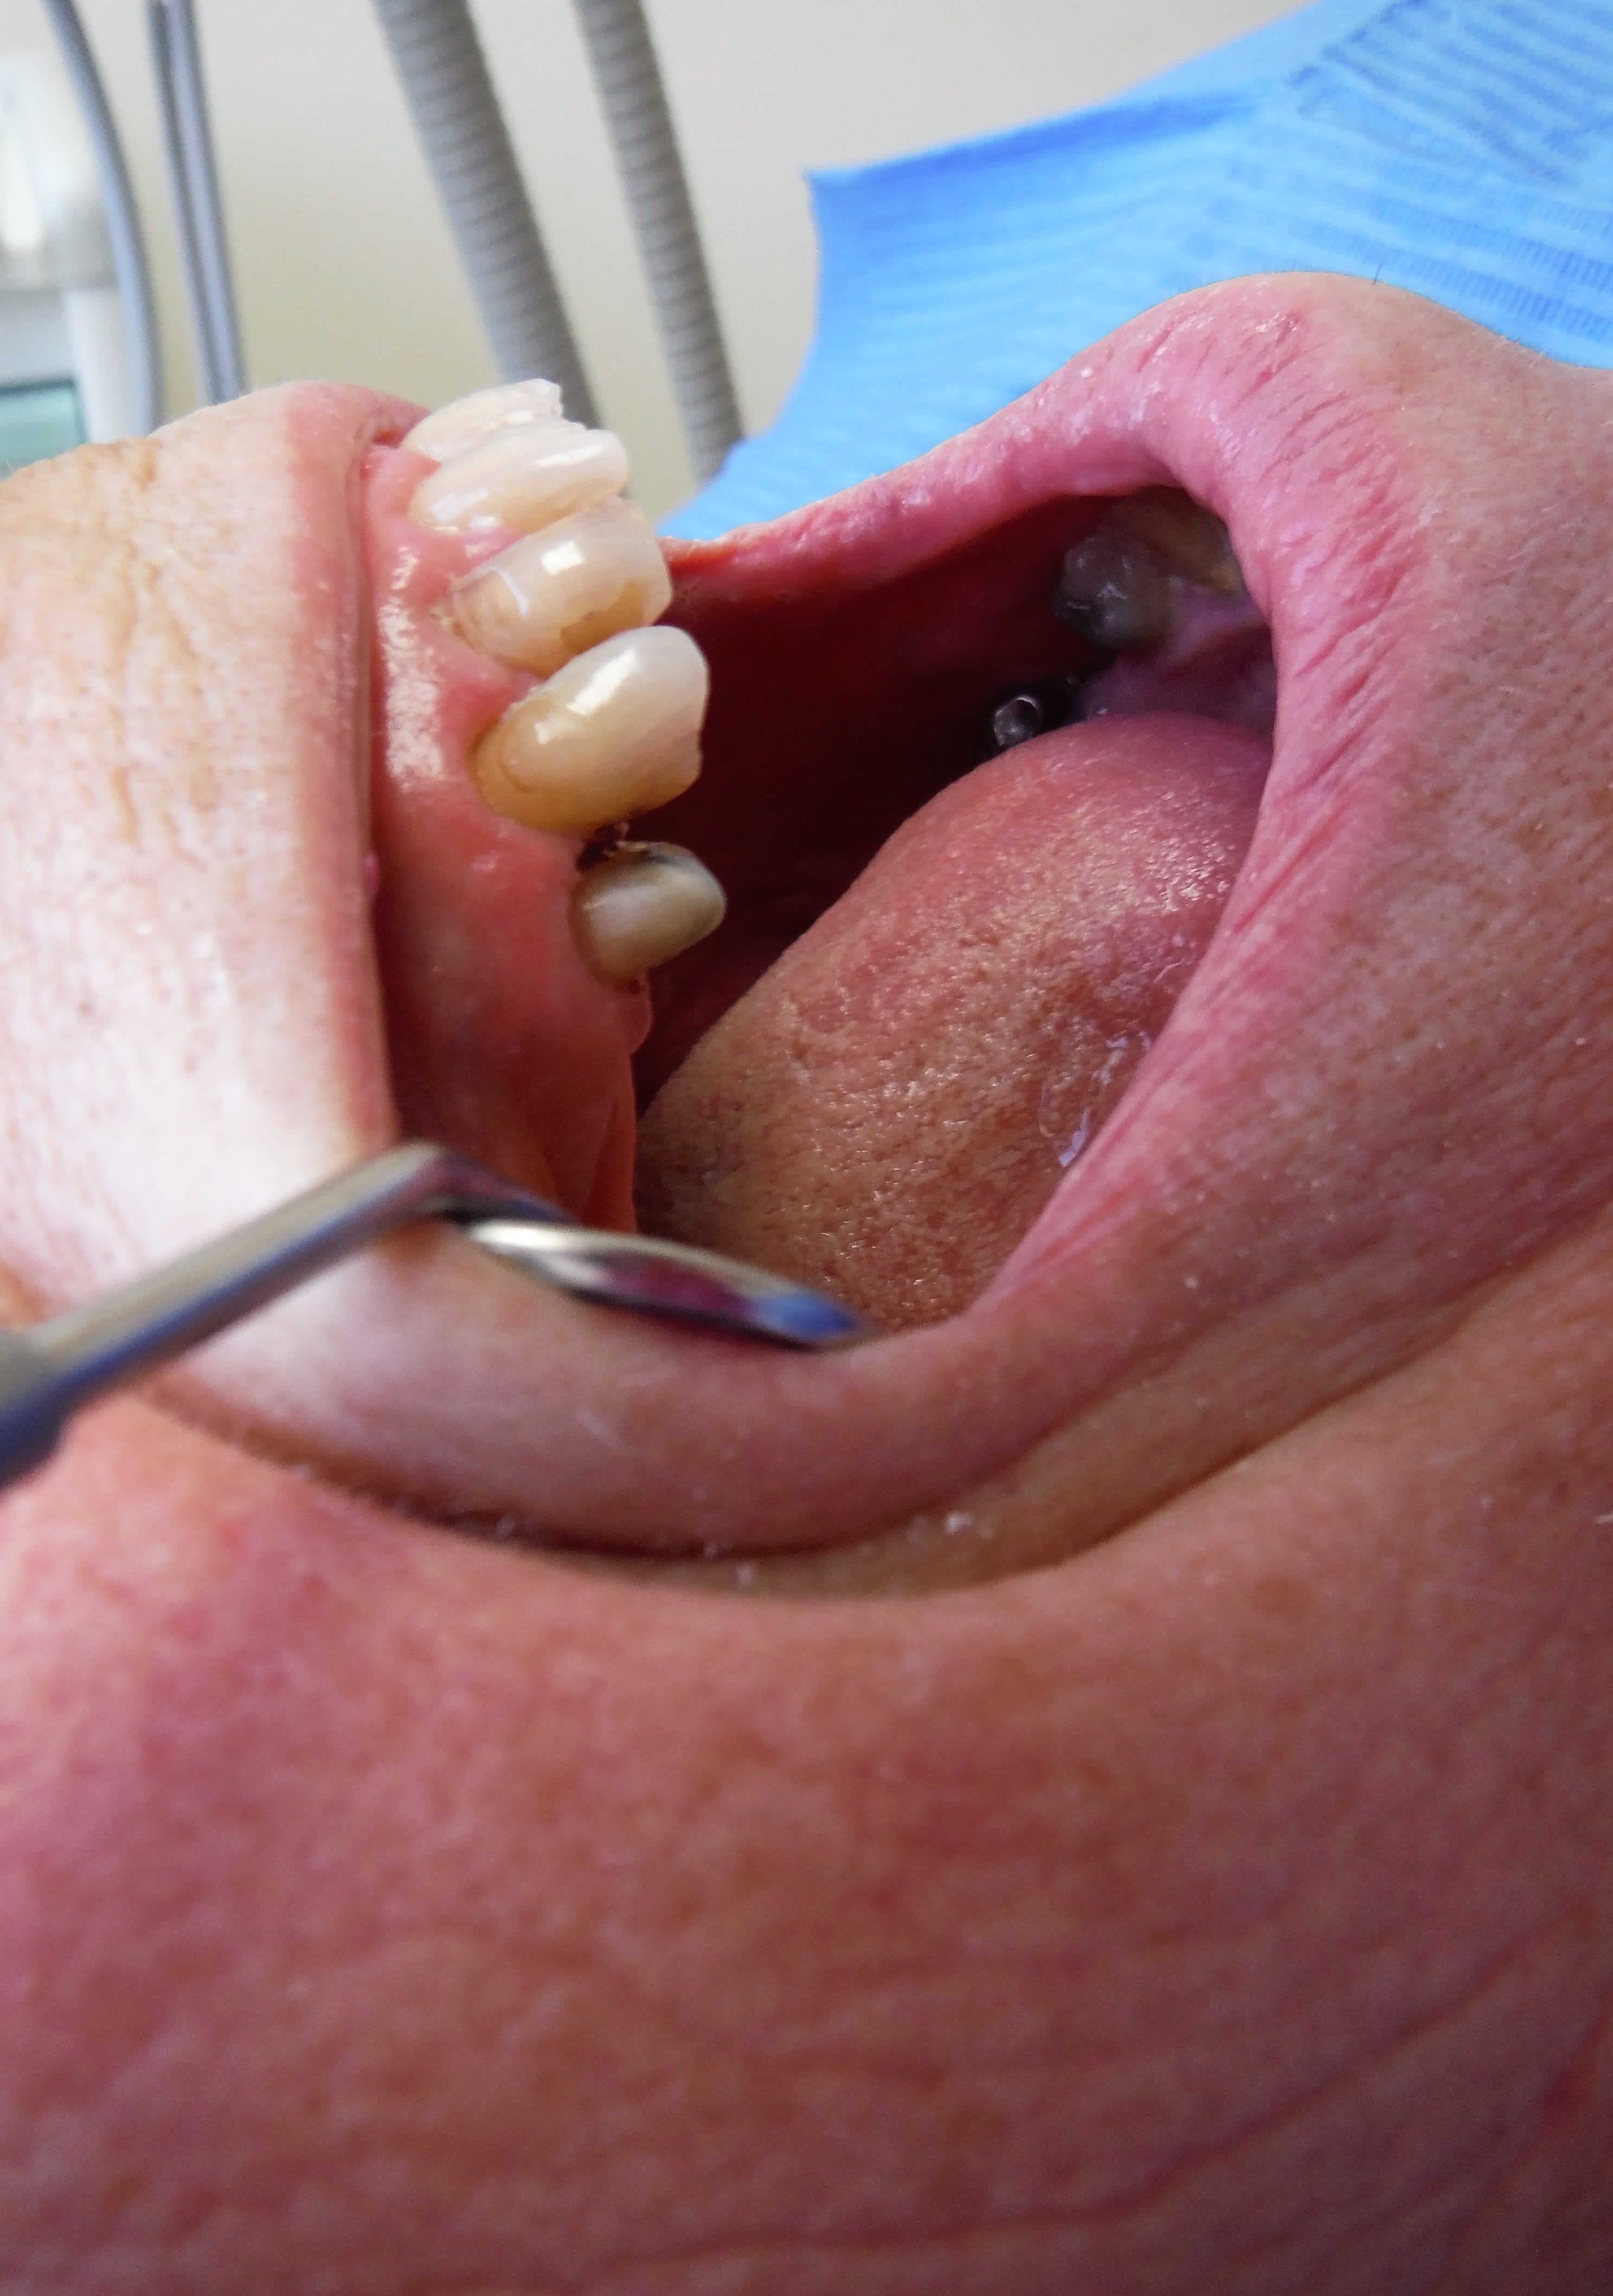

Tiens regarde, la photo est bof bof.

Il manque la 24, la 23 est très usée, pour moi non reconstituable durablement mais pas à dévit, donc indication de CR et voilà mon pilier antr, la 25 sera aussi pilier sur dent vivante.

Là j’appâte le "enlaye", ça devrait mordre ;-))

Pour toi oui. -) pour moi c'est compo ou endo ( doute sur l'avenir de la vitalité pulpaire) puis pareil sur la 25 ( doute sur la vitalité après préparation périphérique) et 2 ic coiffes sous le bridge car une fois les endos faites elles ne sont plus reconstituables durablement et les ic sont indiqués comme piliers de bridges. . . -) ( pas de sc 33 sur 25 car contre indiqué comme pilier de bridge)

C'est marrant mais ta photo confirmerait l'impression de la radio à un CDC et tu te choperais un indu doublé d'une mutilation volontaire. -)

Ce qui ne serait pas le cas avec un doute sur la vitalité pulpaire. Vas t'en prouver le contraire. les cas sont légions de nécroses pulpaires suite à usure ou abrasion. -)

Je pense que le contexte occlusal a aggravé les abrasions, abfractions, ce qui contre-indique les facettes et fera décoller les compos, non crois moi, une CR est souhaitable!-)

Et un implant, si il le pilonne pareil... la prothèse morte... il y aura de la casse, à mon avis sur les 23 et 25 (une petite pièce sur la 25 "ho! Vous n'avez pas de chance! A peine fini, celle d'à coté qui casse... vraiment c'est pas de chance! Bon, bah implant!-))

Si Enlaye était là, il te le dirait, la ferraille en bas à droite est pas équilibrée, sous-occ ou interférence, et le patient surcharge ses 21 22 23, si compos cela décollera, et si facettes, alors là c'est Noël, bonjour le SAV!